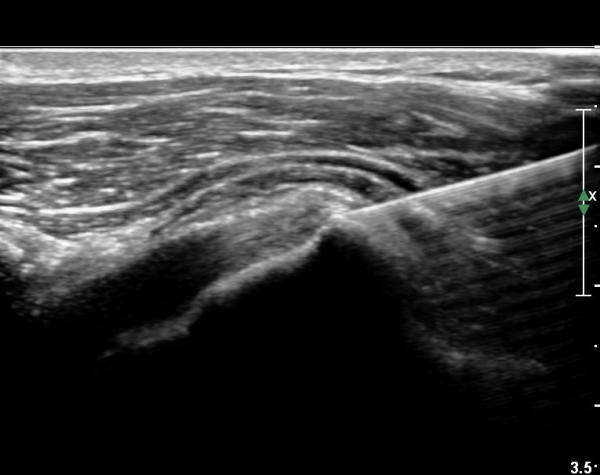

¼®È¸ À§ÂÊ(¸Ó¸®ÂÊ)ÀÇ ÈûÁÙÀÇ Àú¿¡ÄÚ º¯È­°¡ °üÂûµÈ´Ù(»çÁø 4, 5).

Á¡¾×³¶³» ÁÖ»ç ÈÄ ÁÖ»ç¹Ù´ÃÀ» ¹Ýº¹ÀûÀ¸·Î ´õ ÁøÀÔ½ÃÄÑ ¼®È¸¸¦ ÀÚ±ØÇÏ´Â ¸ð½À(»çÁø 5, 6)

¼®Á¡¾×³¶³» ÁÖ»çÄ¡·á(ÂüºÎÆÄÀÏ 1)ÈÄ ¼®È¸ÀÚ±ØÄ¡·á(÷ºÎÆÄÀÏ 2) ¿µ»ó